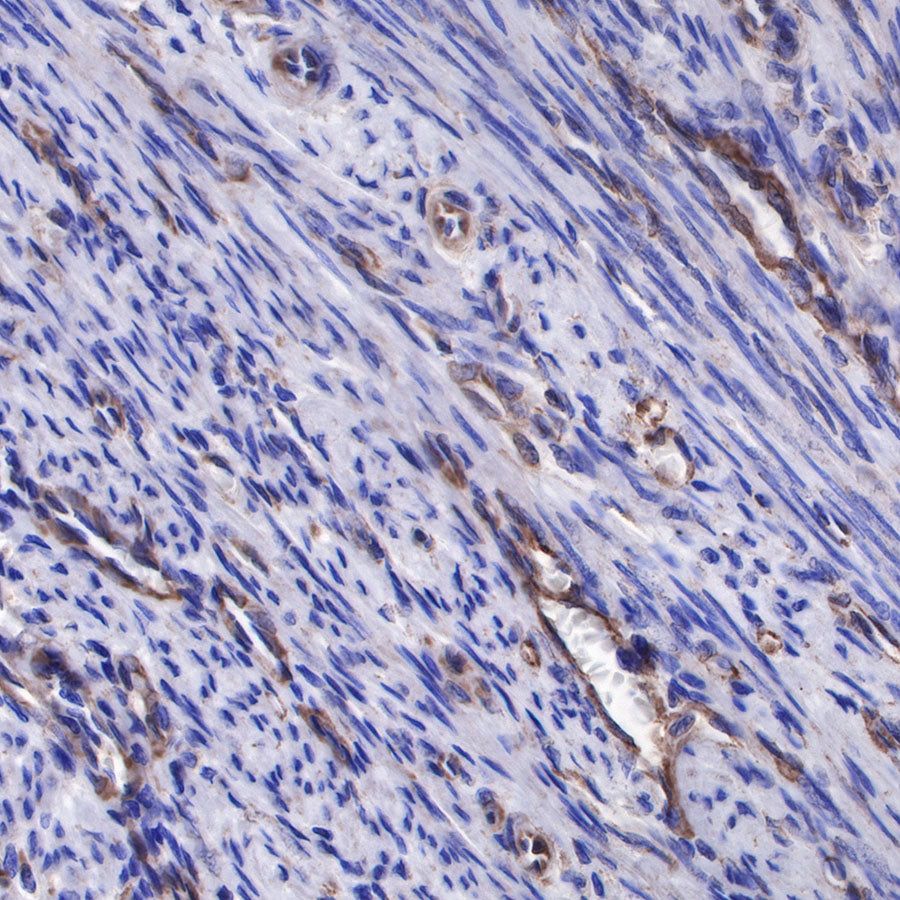

IHC shows positive staining in paraffin-embedded human breast cancer. Anti-sFlt-1/VEGF Receptor 1 antibody was used at 1/1000 dilution, followed by a HRP Polymer for Mouse & Rabbit IgG (ready to use). Counterstained with hematoxylin. Heat mediated antigen retrieval with Tris/EDTA buffer pH9.0 was performed before commencing with IHC staining protocol.